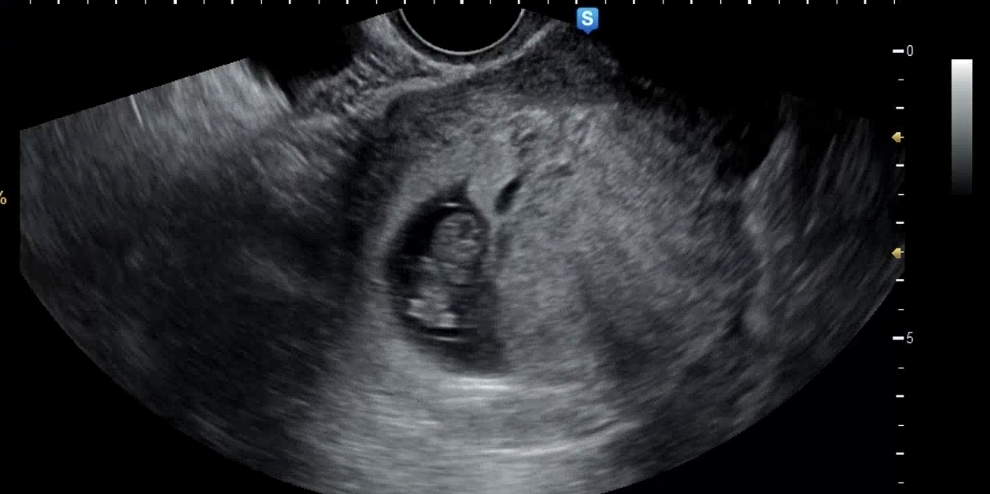

| 가슴 떨리는 임신 이야기를 공유해 주세요. | 둘째를 가질까 말까 하는 고민은 누구나 하실 것 같습니다. 저희 부부도 긴 고민 끝에 “세 번만 시도해보자”라는 마음을 먹었는데, 둘째라 그랬는지 두 번 만에 성공하게 되었어요^^ |

| 치료 도중 느꼈던 가장 기뻤던 순간과 절망적인 것들은 무엇인가요? 잊지 못할 경험이 있나요? | 가장 기뻤던 순간은 임신테스트기에서 선명한 두 줄을 확인했을 때였습니다. 눈물이 핑 돌 정도로 가슴이 떨리던 순간이 아직도 생생합니다. 반대로 절망적이었던 경험은 첫 번째 시도에서 실패 소식을 들었을 때였습니다. 하지만 포기하지 않고 다시 도전했기에, 둘째는 생각보다 빨리 만날 수 있었습니다. |